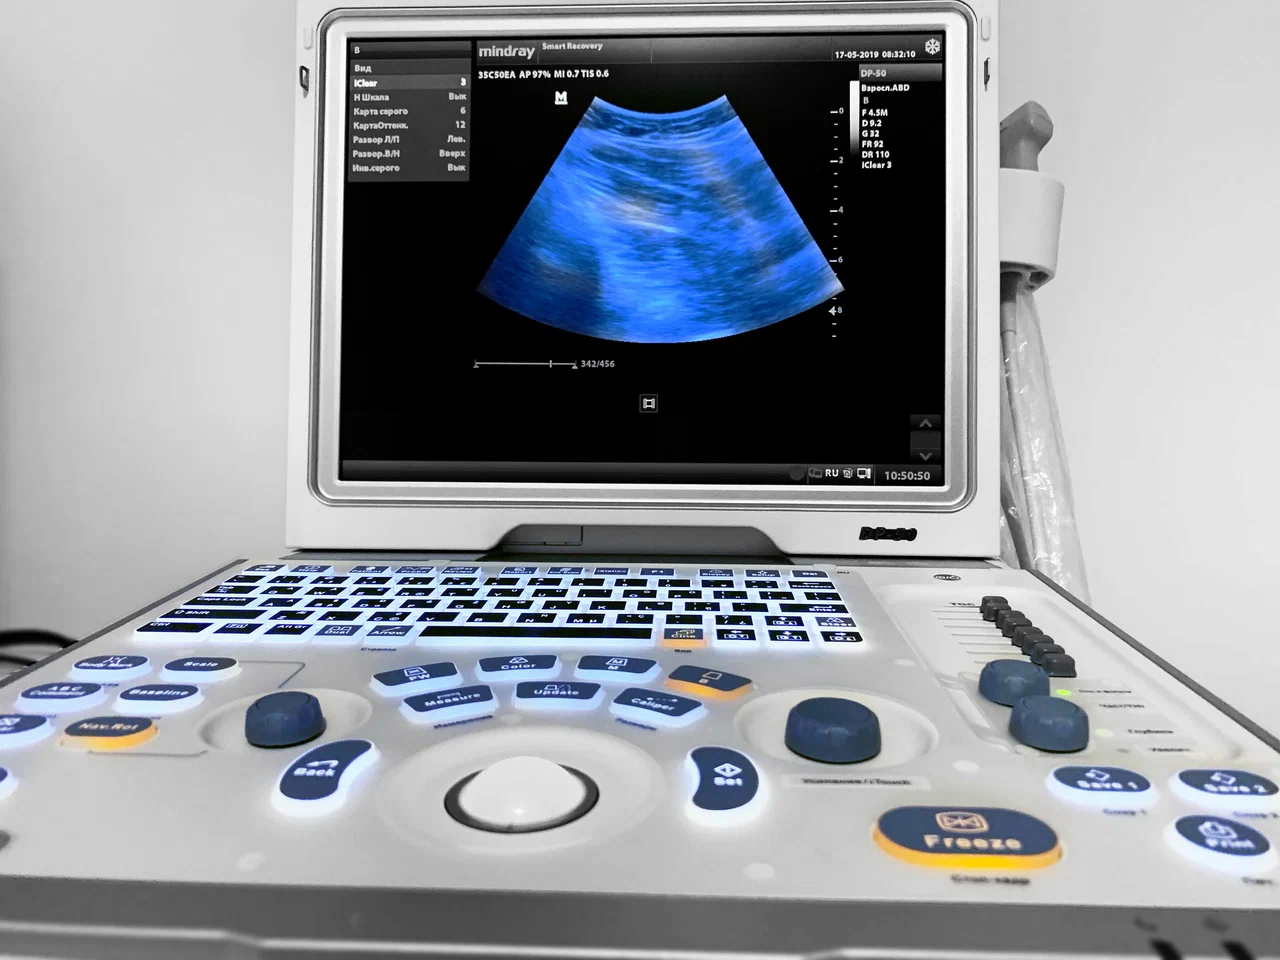

Современные технологии УЗИ в Smart Recovery

Диагностика травм и функциональных изменений требует применения высокоточного оборудования. В клинике используется универсальный ультразвуковой сканер Samsung V7-RUS, разработанный компанией Samsung Medison Co., Ltd.

Аппарат оснащён:

• высокочувствительными датчиками для поверхностных и глубоких структур;

• мощным процессором обработки изображений;

• современными алгоритмами цифровой визуализации;

• возможностью детальной оценки мягких тканей, суставов и сосудов.

Это позволяет выявлять минимальные изменения структуры мышц, сухожилий и связок, начальные стадии воспалительных процессов и перегрузок, которые могут быть неочевидны при стандартных методах обследования.